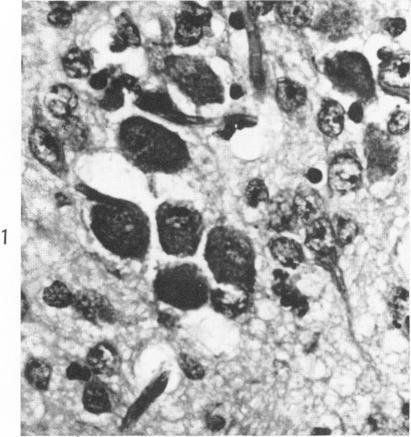

REOVIRUS ENCEPHALITIS IN NEWBORN MICE: AN ELECTRON MICROSCOPIC AND VIRUS ASSAY STUDY.

Am J Pathol. 1965 Aug;47(2):223-39.